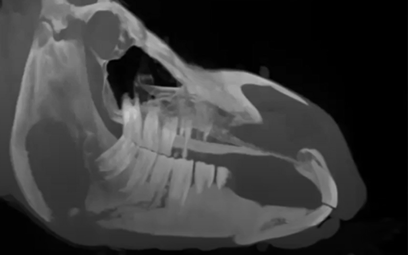

Read MoreThis was an older mare that sustained trauma to her mandible in the pasture. CT images show a draining tract and sequestrum, the tooth above the draining track was removed.

Featured: Dr. Travis Henry, University of Wisconsin-Madison